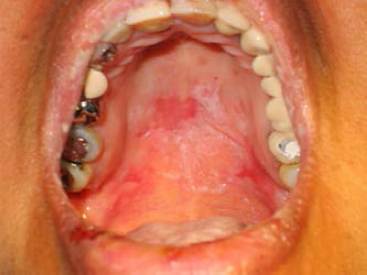

Clinically, head, neck, face, and limb injuries were observed; in the mouth, they were located on the lips, tongue, jugal mucosa, and palate. These lesions were ulcerated, painful, erythematous, bleeding to the touch, and some bullous (Figures 1and2).

Incisional biopsies of the oral lesions were performed, and the diagnosis was blistered with suprabasal acantholysis, which is compatible with pemphigus vulgaris (Figure 3). Histological sections showed a typical intraepithelial cleft, with rounded acantholytic epithelial cells located within the cavity. A moderate underlying infiltration of inflammatory cells was observed. Tests were made for the research of autoantibodies, with negative results.